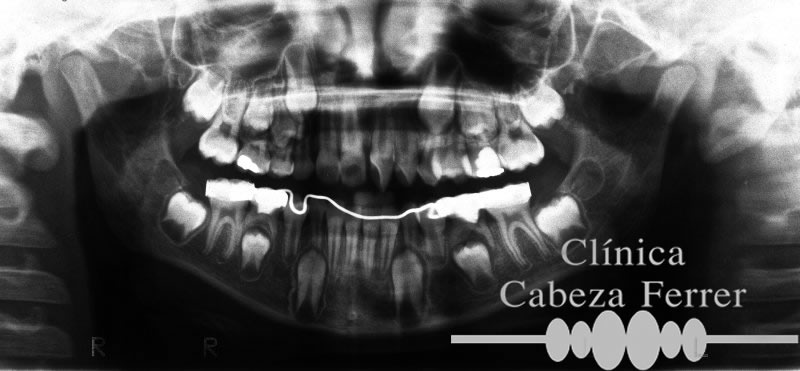

Por tanto en caso de extracciones de muelas de leche, habrá de conservarse el espacio con un aparato que se llama “mantenedor de espacio”. De esta forma se conseguirá que el diente definitivo ocupe el espacio que le corresponde y se coloque adecuadamente con lo que se evitaría un tratamiento ortodóncico.